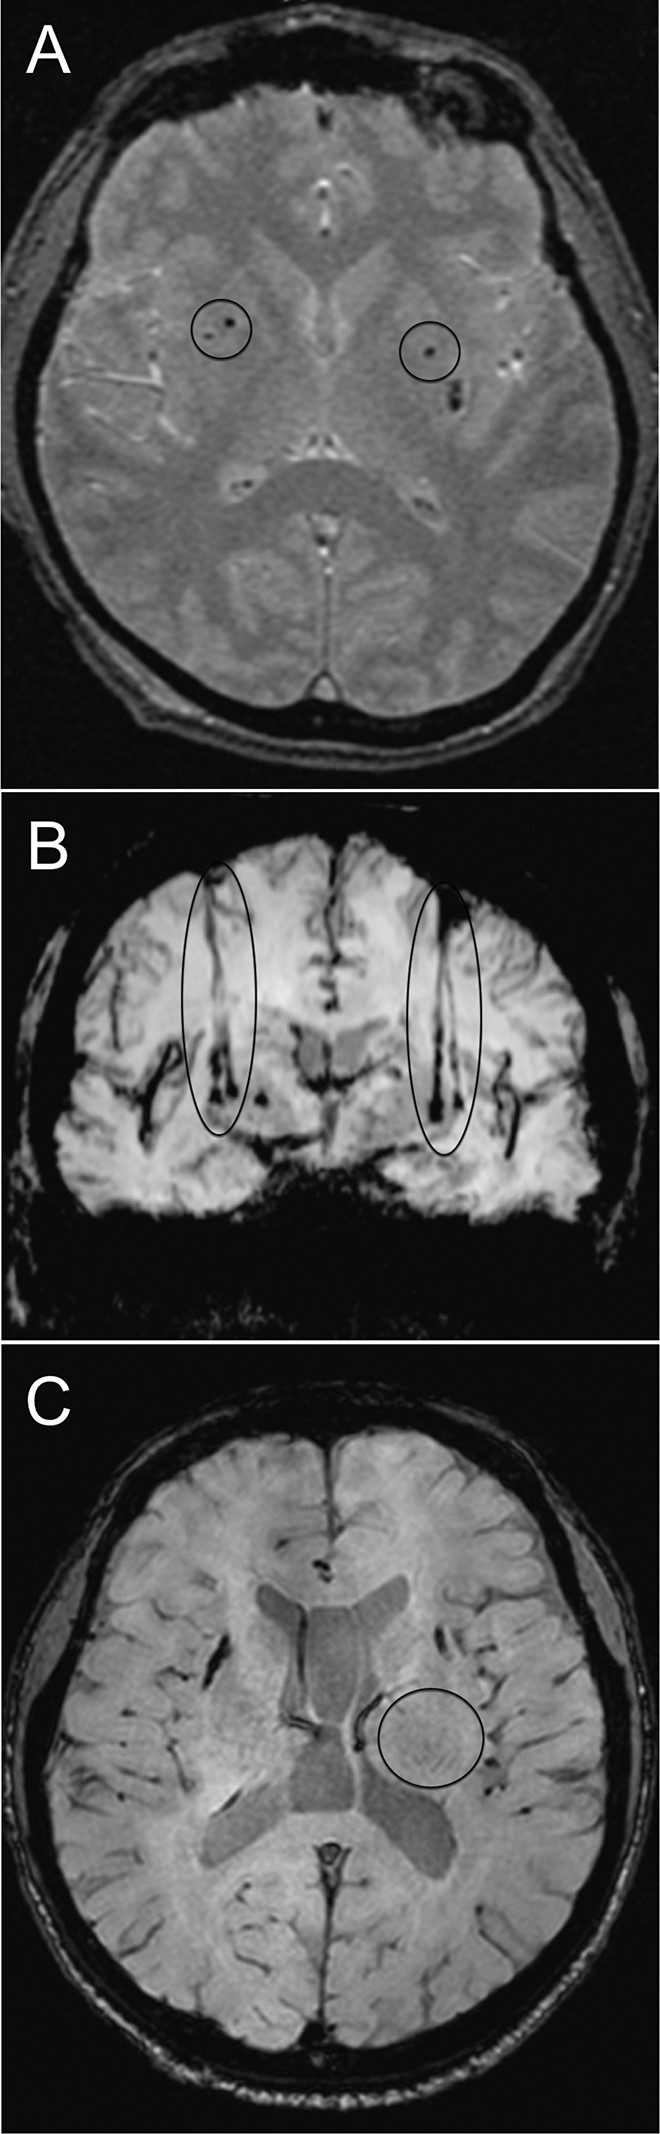

磁共振成像

移植患者的代表性腦部 MR 圖像

如圖2所示。細(xì)胞植入的位點和軌跡路徑如圖 1 和 2 所示。分別參見圖 2A 和 2B。在1、2和4年隨訪的幾個針跡結(jié)束時,在 T2 加權(quán)圖像上識別出小簇低信號。在 P4 的年度 MRI 監(jiān)測中,在右側(cè)殼核(圖2C)中觀察到強大的移植物生長,沒有大腦結(jié)構(gòu)的異常。未顯示腫瘤形成的證據(jù)。